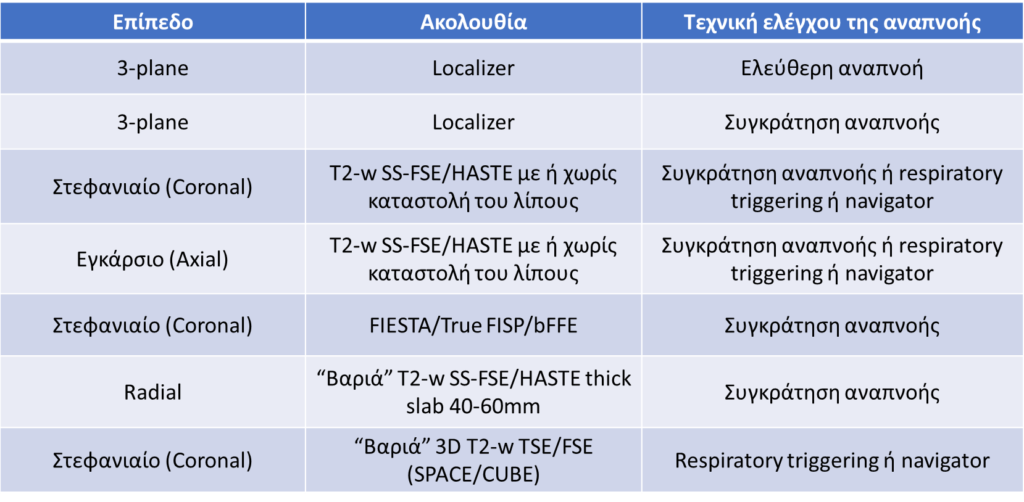

• Ένα τυπικό πρωτόκολλο MRCP παρουσιάζεται στον παρακάτω πίνακα.

• Λόγω της φυσιολογικής αναπνοής του ασθενούς, οι εξετάσεις MRCP πρέπει να διενεργούνται με χρήση τεχνικών ελέγχου της αναπνευστικής κίνησης. Οι ακολουθίες με συγκράτηση της αναπνοής πρέπει να σχεδιάζονται στο localizer που λήφθηκε με συγκράτηση της αναπνοής, ενώ οι ακολουθίες με respiratory triggering/navigator στο localizer που λήφθηκε με ελεύθερη αναπνοή. Η προτεινόμενη τεχνική ελέγχου της αναπνοής για την κάθε ακολουθία αναγράφεται στον παρακάτω πίνακα.